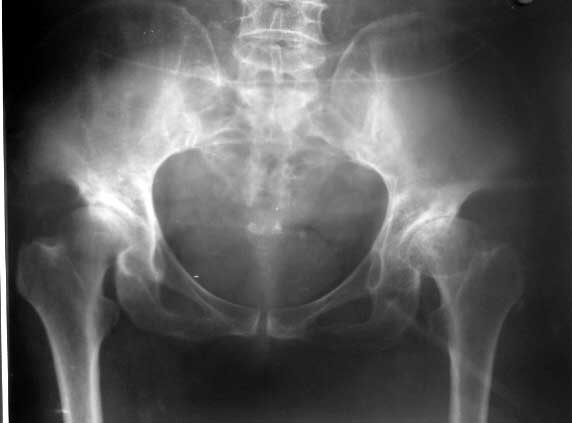

以下是引用yxfjnchina在2005-4-16 19:51:36的发言:[br]双侧髋臼稍浅平,髋臼外上缘可见骨质增生.左股骨头内密度不均,可见小囊状低密度影及不均匀硬化.小梁紊乱.考虑双侧髋臼发育不良并退行性骨关节病.左股骨头缺血性坏死待排

以下是引用dgma在2005-7-1 21:34:00的发言:[br][br]双侧髋臼发育不良。[br]退行性骨关节病。[br]左股骨头缺血性坏死?[br]建议:左股骨头mr扫描。